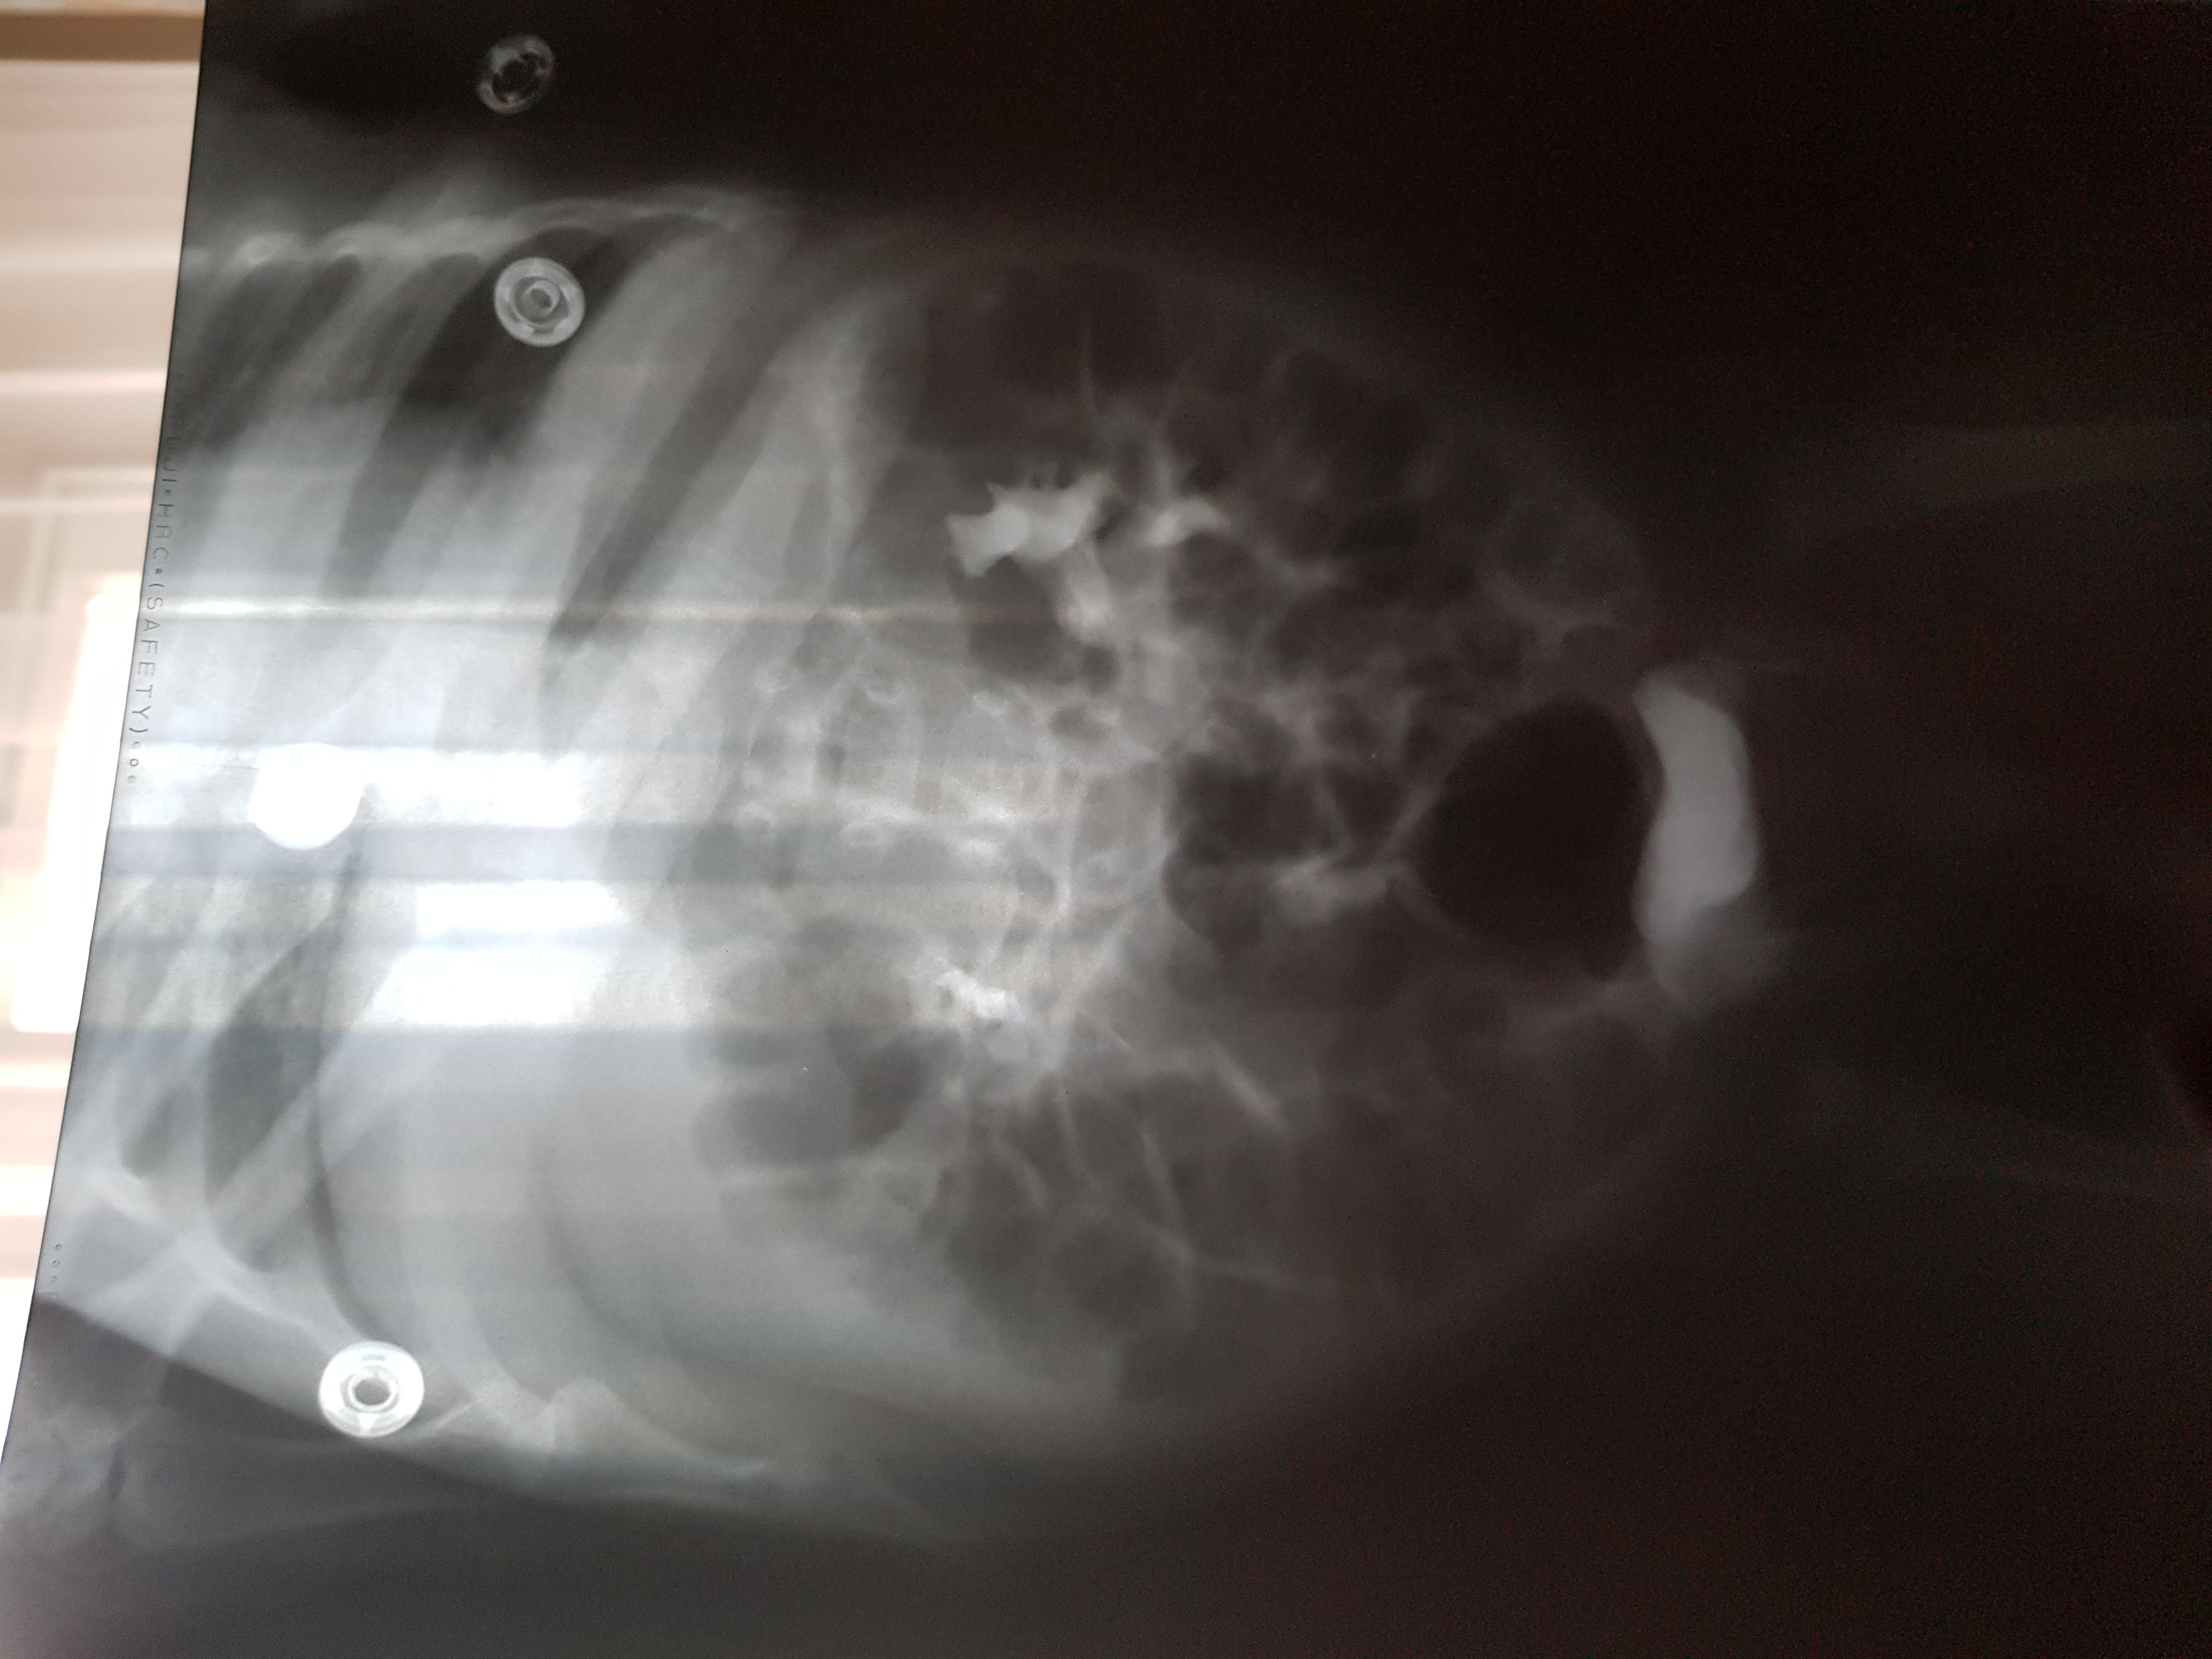

Добрый день! Еще внутриутробно у ребенка обнаружили расширение лоханок.Провели обследование в 1.5 месяца.Поставили диагноз болезнь Ормонда.И назначили консервативное лечение.В 2ух мочеточниках по несколько наростов.рефлюкса не было.Скажиье, возмлжнл что ребенок поосто перерастет?

Болезнь Ормонда (ретроперитонеальный фиброз, забрюшинный фиброз) – хроническое воспаление жировой клетчатки забрюшинного пространства, которое постепенно приводит к компрессии и нарушению проходимости трубчатых структур данного анатомического участка. Чаще всего, в качестве этих тубулярных структур выступают мочеточники.

У меня есть сомнения, что причиной гидронефроза в Вашем случае явилось именно это состояние.